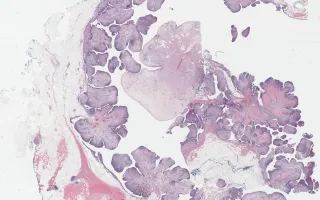

Breast, Malignant phyllodes tumour

Malignant phyllodes tumour

7.4 cm right breast lump.

Phyllodes tumours are fibroepithelial tumours that arise from intralobular stroma of the breast. The lesions have a 'leaf like' configuration, hence the Greek name 'phyllodes.' They mostly occur in the sixth decade, but can occur at any age. Criteria to differentiate between benign, borderline, and malignant include the degree of stromal cellularity and atypia, mitotic count, stromal overgrowth, and the nature of their tumour borders. While benign and borderline phyllodes tumours recur locally and rarely metastasize, malignant phyllodes tumours can develop distant metastases in about 15% of the cases. Excision with wide (at least 1 cm) margins with no lymph node dissection is the treatment of choice for malignant phyllodes tumours, with adjuvant radiation therapy sometimes given to large (over 10 cm) lesions or lesions with incomplete excision.

Findings in this case suggestive of malignancy include: marked hypercellularity, marked nuclear atypia, high mitotic count (up to 21 mitotic figures per 10 HPF), stromal overgrowth, infiltrative borders and heterologous elements in the form of adipocytes.